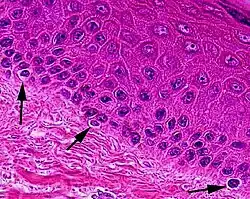

Melanocytes are melanin-producing neural crest-derived[3] cells located in the bottom layer (the stratum basale) of the skin's epidermis, the middle layer of the eye (the uvea),[4] the inner ear,[5] vaginal epithelium,[6] meninges,[7] bones,[8] and heart found in many mammals and birds.[9] Melanin is a dark pigment primarily responsible for skin color. Once synthesized, melanin is contained in special organelles called melanosomes which can be transported to nearby keratinocytes to induce pigmentation. Thus darker skin tones have more melanosomes present than lighter skin tones. Functionally, melanin serves as protection against UV radiation. Melanocytes also have a role in the immune system.

Typically, between 1000 and 2000 melanocytes are found per square millimeter of skin or approximately 5% to 10% of the cells in the basal layer of epidermis. Although their size can vary, melanocytes are typically 7 μm in length.

Both lightly and darkly pigmented skin contain similar numbers of melanocytes,[12] with difference in skin color due to differences the packing of eumelanin into the melanosomes of keratinocytes: those in dark-toned skin are "packaged into peri-nuclear distributed, ellipsoid" melanosomes while those light-tone skin are "assembled into clustered small, circular melanosomes".[13] There are also differences in the quantity and relative amounts of eumelanin and pheomelanin.[13] Pigmentation including tanning is under hormonal control, including the MSH and ACTH peptides that are produced from the precursor proopiomelanocortin.